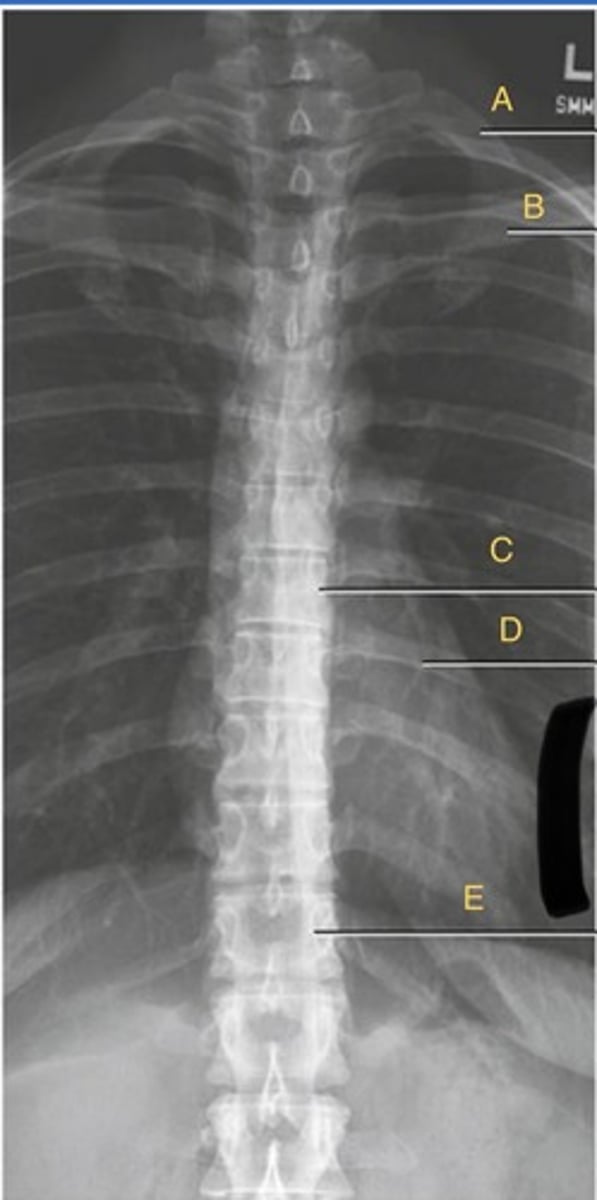

L 1st rib

A.

L clavicle

B.

T8 body

C.

T9 L posterior rib.

D.

T12 body

E.

AP T-spine

What position?